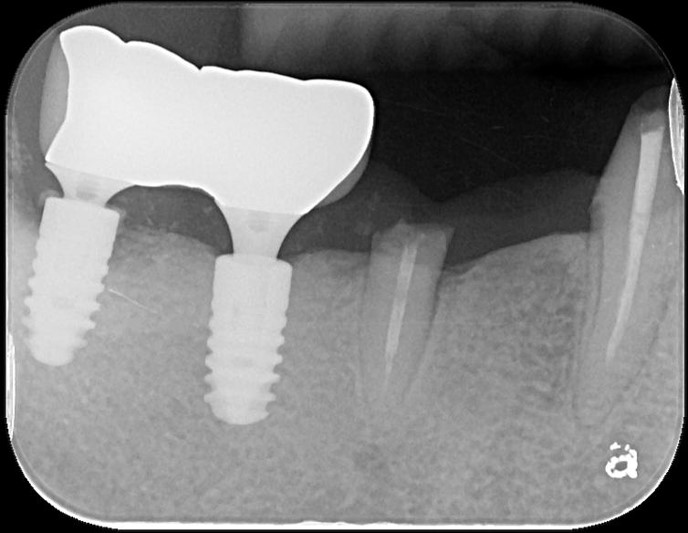

術後X光